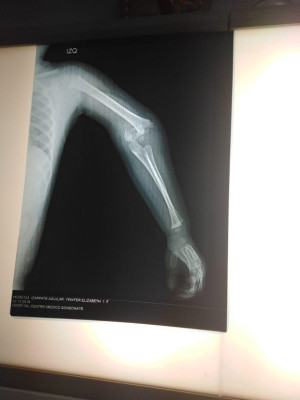

Imágenes de ortopedia y traumatología

Envíado por Dr. José Israel Flores Hernández